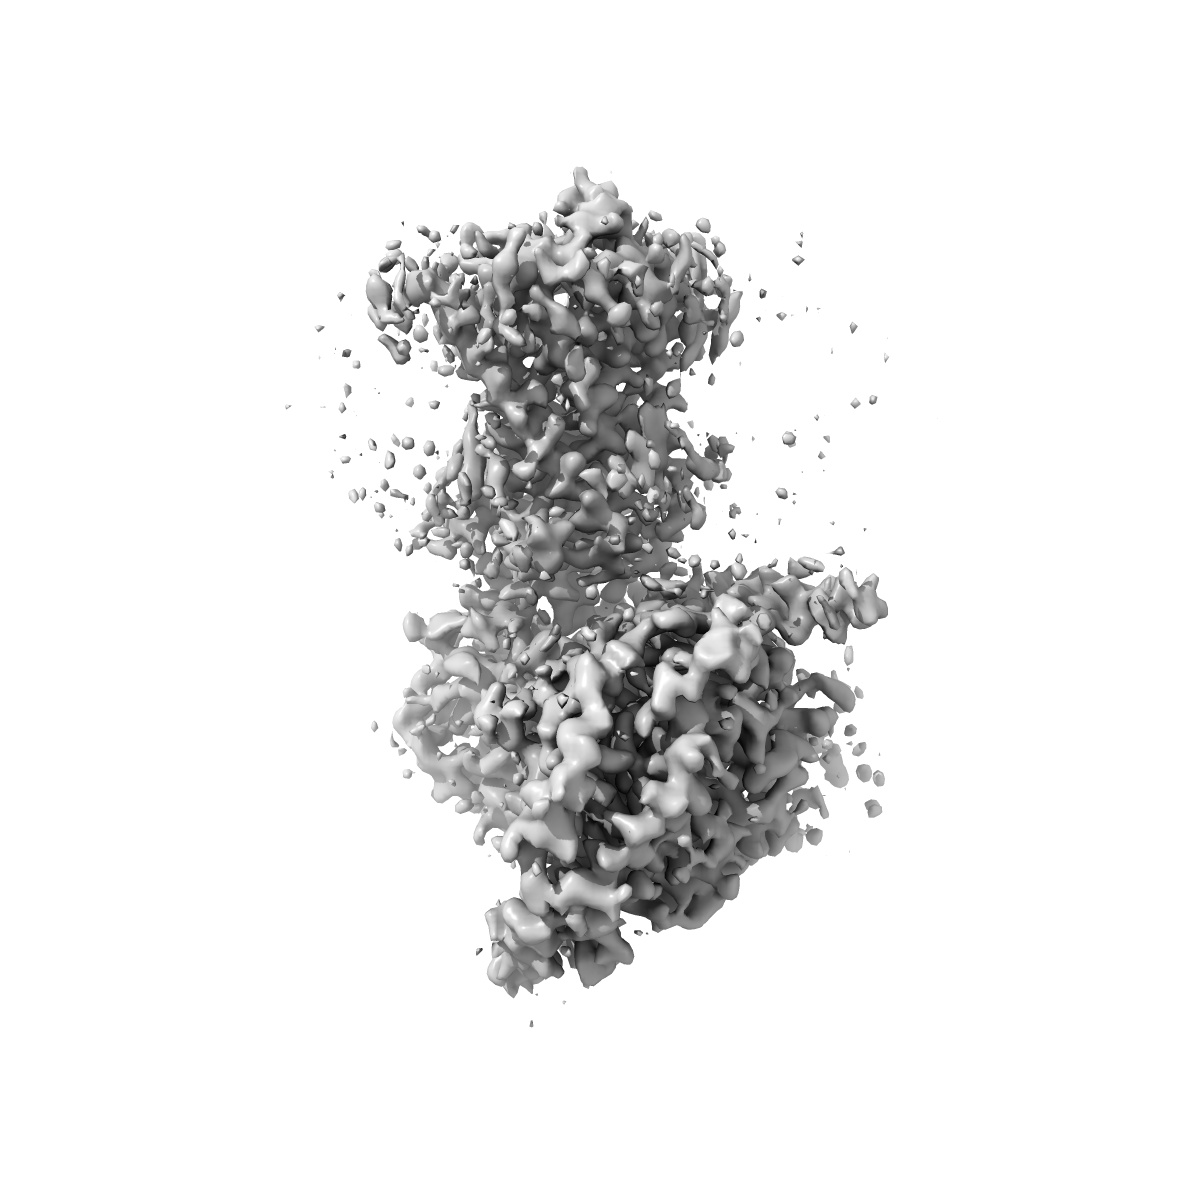

CryoEM structure of beta-2-adrenergic receptor in complex with GTP-bound Gs heterotrimer (Class J)

Sample: Complex of beta-2 adrenergic receptor and Gs heterotrimer with GTP

Fitted models: 8unu

Time-resolved cryo-EM of G-protein activation by a GPCR.